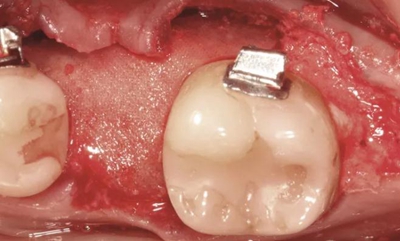

圖2a.病例1中,同期牙槽嵴增量和右下第一磨牙種植位點加速磨牙直立。術(shù)前臨床檢查顯示修復空間小、牙槽嵴吸收

圖2b.增量時,在受區(qū)和右下第二磨牙遠中進行牙槽嵴去皮質(zhì)術(shù)

圖2c. 移植處用膠原膜保護,磨牙后區(qū)用硫酸鈣覆蓋

圖2d. 3個月后,獲得顯著的骨增量,同時創(chuàng)造出1.6mm的近遠中修復空間